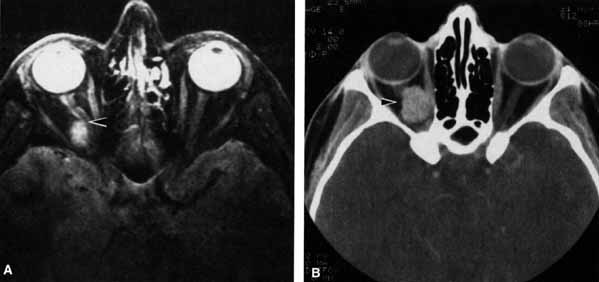

Pupillary dilation and reduction of accommodation occur when parasympathetic innervation to the globe is damaged. When the damage occurs at or distal to the ciliary ganglion, Adie's pupil results. The pupil contracts poorly to light but better to accommodation. The pupil movements are slow and poorly coordinated (vermiform). Generally there is a reduction in accommodation range. The pupil in such cases develops a supersensitivity to parasympathomimetics such as 0.1% pilocarpine. Orbital trauma, inflammation, and intraocular laser treatment may result in Adie's pupil. Deep orbital dissection lateral to the optic nerve in the region of the ciliary ganglion or around the anterior optic nerve where the short ciliary nerves run may also produce Adie's pupil. The denervation may only be sectoral, resulting in an abnormally contoured pupil which demonstrates slow tonic contracture only in the involved sector. Because the parasympathetics have diverged from cranial nerve III prior to entering the ciliary ganglion, pupillary dilation which contracts with 0.1% pilocarpine is not usually associated with neurogenic ophthalmoplegia (Fig. 19).

Fig. 19 A. A patient underwent endoscopic exploration of the right ethmoid and maxillary sinus for persistent epistaxis. Postoperatively the patient demonstrates right proptosis, restricted extraocular movements of the right eye, and a dilated right pupil. Instillation of 0.1% pilocarpine resulted in miosis on the right and no change on the left. Computed tomography (CT) shows a vessel clip lateral to the optic nerve (arrow), near the position of the ciliary ganglion. B. Coronal CT scan showing the clip lateral to the optic nerve (arrow).